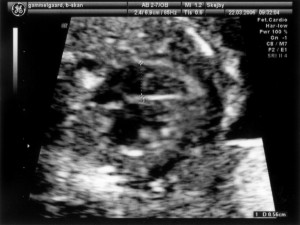

Baby ligger med hovedet nederst i midten og kigger op. Hun flekser så meget i ryggen at hendes ben går helt op over hovedet. Babys hjerte med nogle målinger.